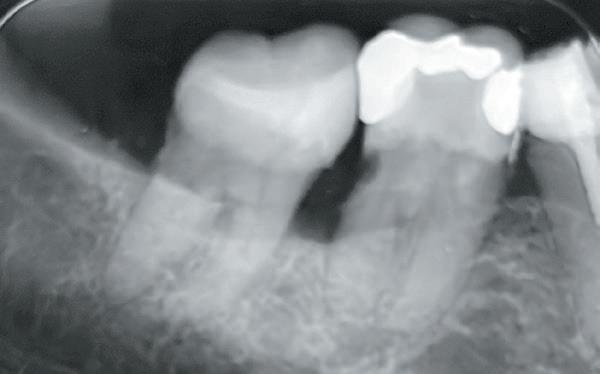

Voordat je aan een wortelkanaalbehandeling begint, zorg je voor (of maak je) een goede beginfoto waar het te behandelen gebitselement volledig op staat afgebeeld. Deze foto geeft essentiële informatie: de grootte van de pulpakamer en de ligging ervan; het aantal en de vorm van de wortels en de breedte van hun wortelkanalen en de lengte van de wortels. Hiermee kan je de DETI-score bepalen en de moeilijkheidsgraad inschatten. De grootte en de ligging van de pulpakamer op de röntgenfoto in combinatie met de ideale anatomische vorm, zoals in foto 1 is aangegeven, bepaalt de uiteindelijke vormgeving van de opening. Bij de molaren liggen de kanaalingangen in de buurt van de knobbeltoppen. Als die niet meer in originele staat

De verwijzend tandarts is bezig om een wortelkanaalbehandeling uit te voeren in gebitselement 27. Er zijn vier kanalen gevonden, maar helaas breekt er in het mesiobuccale kanaal (MB 1) een WaveOne vijltje af, maat geel (foto 2). Het lukt de tandarts niet om

1. De locatie van de kanaalingangen ten opzichte van de occlusale morfologie (rood). In zwart is de ideale of standaard opening ingetekend. De uiteindelijke vorm van de opening is voorts ook afhankelijk van de klinische situatie, die vooral vanuit een goede begin foto wordt verkregen.

2. Het afgebroken instrument op de foto van de verwijzend tandarts.

3. De opening is vrij klein gekozen. In rood is de ideale opening aangegeven, de tandarts had veel meer restauratiemateriaal mogen wegnemen.

6. Klinische opname waarop het oorspronkelijke verloop en de positie van het afgebroken instrument te zien zijn. Het instrument was in de wand ‘geschroefd’. Door de te kleine opening moet het ‘roterend’ instrumentarium onnodig veel buigen en komt er veel druk op de vijl

staan, waardoor ze makkelijk kunnen breken. Zorg voor een ‘straight line access’ ofwel een rechte toegang.

7. Hierop is nog eens de correcte opening te zien. Ik heb veel van het aanwezige amalgaam weggenomen om zoveel mogelijk ruimte te krijgen. Ook is te zien hoe ik het mesiobuccale kanaal heb moeten verbreden om bij het instrument te komen. Het palatinale kanaal is niet zichtbaar op deze afbeelding.

het vijltje te verwijderen. De patiënte wordt verwezen voor het afmaken van de wortelkanaalbehandeling.

Als ik de patiënte zie, valt me op dat de opening die de tandarts gemaakt heeft, nogal klein is (foto 3). Eigenlijk is daar niet zoveel reden toe; als ik een ideale opening inteken (in rood), dan loopt een groot deel door restauratiemateriaal. Overwogen kan worden om de aanwezige mesiale box met restauratiemateriaal weg te halen als dat het zicht op de pulpakamer vergroot – ik verwijs naar de tip hierboven (wees bij het openen niet spaarzaam met het wegnemen van aanwezig restauratiemateriaal).

Het afgebroken instrument ligt vrij diep; in het onderste 1/3 deel van de wortel. Vaak laten we het afgebroken instrument in het onderste 1/3 deels zitten, omdat verwijderen lastig is en er een kans is op schade. Daarom proberen we het te passeren en wordt het afgebroken instrument onderdeel van de kanaalvulling.

Passeren lukt mij in deze casus helaas niet. Omdat het instrument in een recht deel van het kanaal ligt, waag ik een poging om het afgebroken instrumentje te verwijderen, zodat ik het kanaal kan desinfecteren en kan vullen.

Onder microscopie en met een LN boortje zoek ik het instrumentje op. Na verificatie verwijder ik het door

met een ultrasone tip (Spartan CPR 8, bruin) rondom het vijltje materiaal weg te nemen, waardoor deze als het ware uitgegraven wordt. WaveOne vijltjes zijn irritant om te verwijderen, het nikkeltitanium materiaal wil naar een oorspronkelijke vorm (een rechte vorm) terugbuigen en daarom drukt het zich steeds vast bij het verwijderen. Staal is vaak makkelijker te verwijderen. Maar het lukt me en de wortelkanaalbehandeling kan worden afgemaakt.

Het verwijderen van een afgebroken instrument kost altijd relatief veel (gezond) tandweefsel en kent veel risico op perforatie of andere schade. Daarom is het altijd belangrijk om goed te overwegen of een vijl verwijderd moet worden.

Maar beter nog is om te voorkomen dat een vijltje afbreekt door bij de opening voldoende te prepareren voor goed zicht en voor wat we noemen een ‘straight line access’. Goede voorbereiding is het halve werk.